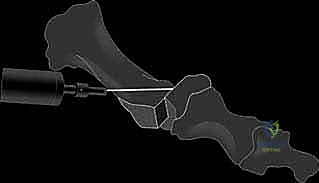

لحسن الحظ، لم يقف الطب الحديث مكتوف الأيدي أمام هذه المعاناة. فقد تطورت التقنيات الجراحية لجراحة العظام بشكل مذهل لتقديم حلول جذرية وفعالة لهذه المشكلة. ومن بين ترسانة الإجراءات الجراحية المتاحة، تتربع "عملية شيفرون البعيدة" (Distal Chevron Osteotomy) على عرش التقنيات الجراحية كإجراء ذهبي وأساسي لتصحيح إبهام القدم الأروح ذو الدرجة الخفيفة إلى المتوسطة. هذه العملية الدقيقة ليست مجرد استئصال للبروز العظمي، بل هي إعادة هندسة شاملة للميكانيكا الحيوية للقدم، حيث يتم قطع العظم بطريقة هندسية دقيقة (على شكل حرف V) وإعادة محاذاته وتثبيته، مما يضمن استعادة الوظيفة الطبيعية للقدم، وتخفيف الألم بشكل نهائي، وتحسين نوعية الحياة للمرضى.

يتكون الشعاع الأول من عظم المشط الأول (First Metatarsal) وسلاميات إصبع القدم الكبير (Phalanges). المفصل الذي يربط بينهما هو المفصل المشطي السلامي الأول (1st MTP Joint)، وهو مسرح العمليات الرئيسي لتشوه إبهام القدم الأروح.

- رأس عظم المشط الأول: هو بنية عظمية مستديرة ومعقدة مغطاة بطبقة ناعمة من الغضاريف الزجاجية التي تسمح بالحركة السلسة. يوجد على سطحه الأخمصي (السفلي المواجه للأرض) تجويفان طوليان مبطنان بالغضاريف، يفصل بينهما نتوء عظمي مستدير يُعرف بالعرف (Crista). هذه التجويفات ليست عشوائية، بل هي مسارات انزلاق حيوية للعظام السمسمية.

* زاوية إبهام القدم الأروح (Hallux Valgus Angle - HVA): هي الزاوية بين المحور الطولي لعظم المشط الأول والمحور الطولي للسلامية الدانية. الزاوية الطبيعية أقل من 15 درجة. في الحالات الخفيفة إلى المتوسطة (التي تناسبها عملية شيفرون)، تتراوح بين 15 إلى 40 درجة.

* الزاوية بين أمشاط القدم (Intermetatarsal Angle - IMA): هي الزاوية بين المحور الطولي لعظم المشط الأول وعظم المشط الثاني. الزاوية الطبيعية أقل من 9 درجات. عملية شيفرون البعيدة مثالية عندما تكون هذه الزاوية بين 9 و 15 درجة.